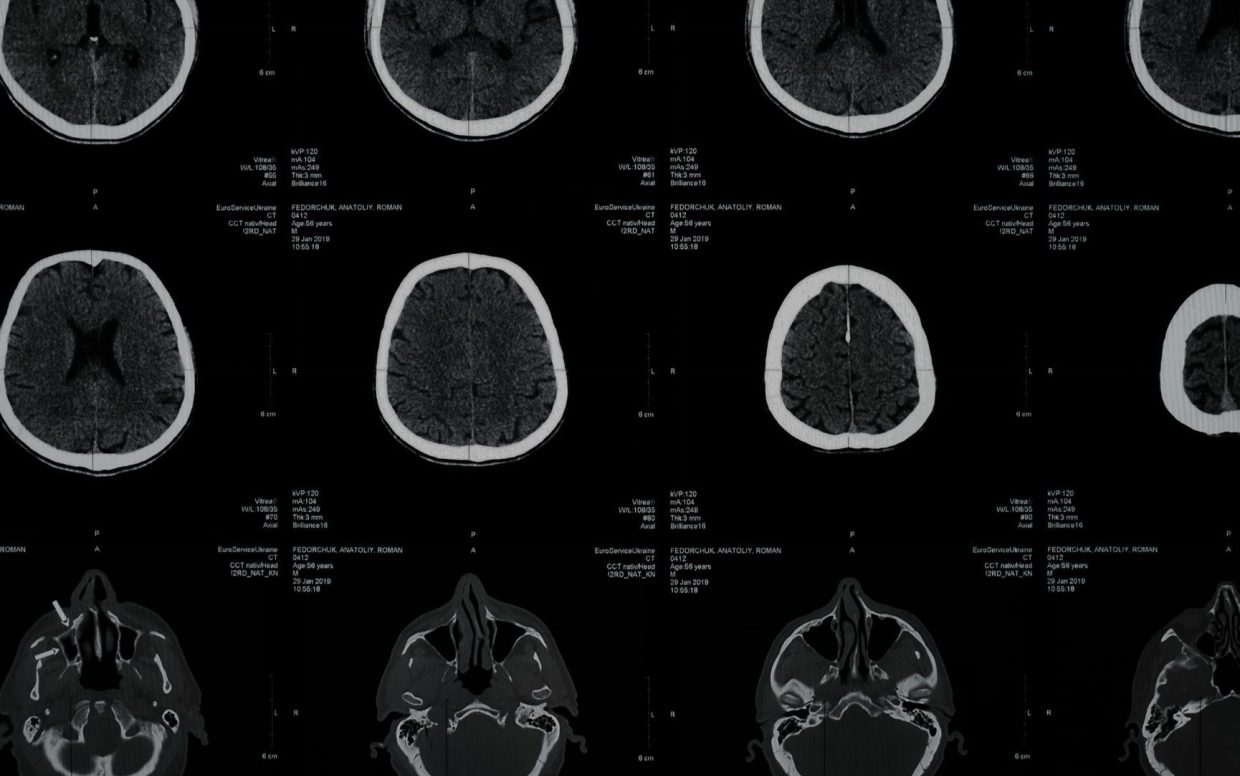

Mae Ymchwil Canser Cymru wedi lansio Menter Ymchwil Tiwmorau'r Ymennydd cyntaf erioed Cymru i ddod â gobaith i bobl sy'n byw gyda thiwmorau'r ymennydd, eu teuluoedd a'u hanwyliaid